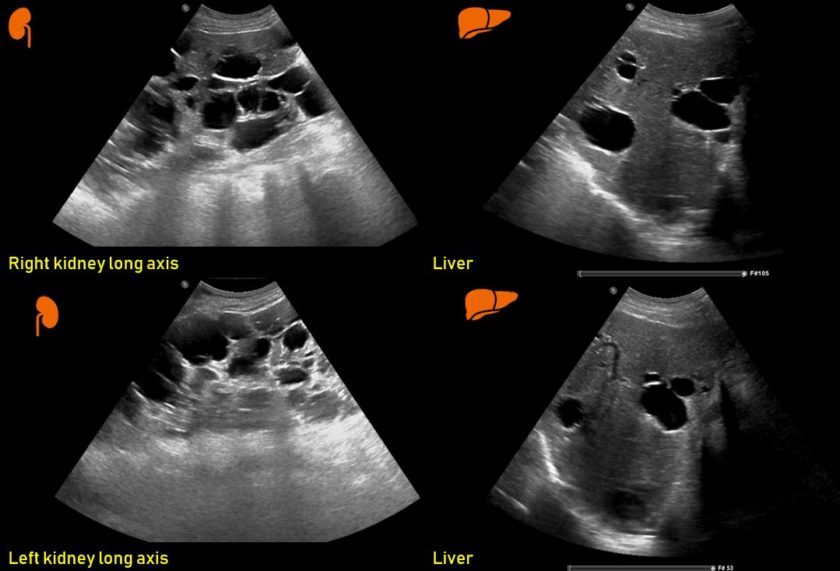

Ultrasound features of Kidney Cysts Renal Fellow Network Vitamin C And Kidney Cysts Kidney cysts are round pouches of fluid that form on or in the kidneys. Cystic kidney disease causes pockets of clear, watery fluid (cysts) to form in the kidneys. They may appear for no clear reason or as a sign of an underlying condition. Simple kidney cysts are commonly observed in normal kidneys, with an increasing incidence as individuals age. Vitamin C And Kidney Cysts.

Ultrasound features of Kidney Cysts Renal Fellow Network Vitamin C And Kidney Cysts They can be small or large and you can have more than one. Kidney or renal cysts are round, fluid filled sacs that can form in the kidneys. But more often, kidney cysts are a type. Cystic kidney disease causes pockets of clear, watery fluid (cysts) to form in the kidneys. Previous studies of vitamin c and kidney stones were. Vitamin C And Kidney Cysts.